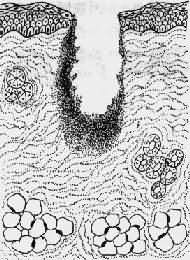

1.一般愈合(healing by first intention)见于组织缺损少、创缘整齐、无感染、经粘合或缝合后创面对合严密的伤口,例如手术切口。这种伤口中只有少量血凝块,炎症反应轻微,表皮再生在24~48小时内便可将伤口覆盖。肉芽组织在第三天就可从伤口边缘长出并很快将伤口填满,5~6天胶原纤维形成(此时可以拆线),约2~3周完全愈合,留下一条线状瘢痕。一期愈合的时间短,形成瘢痕少(图2-5)。

1.创缘整齐,组织破坏少

2.经缝合,创缘对合,炎症反应轻

3.表皮再生,少量肉芽组织从伤口缘长入

4.愈合后少量疤痕形成

图2-5 创伤一期愈合模式图